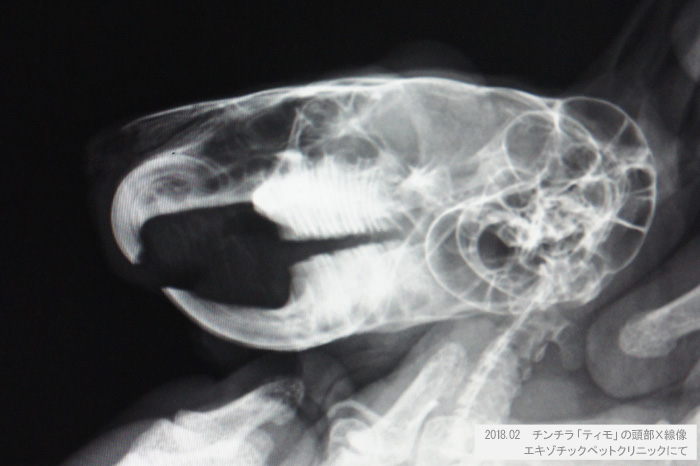

チンチラのティモ 頭部X線像 2018年2月 エキゾチックペットクリニックにて撮影